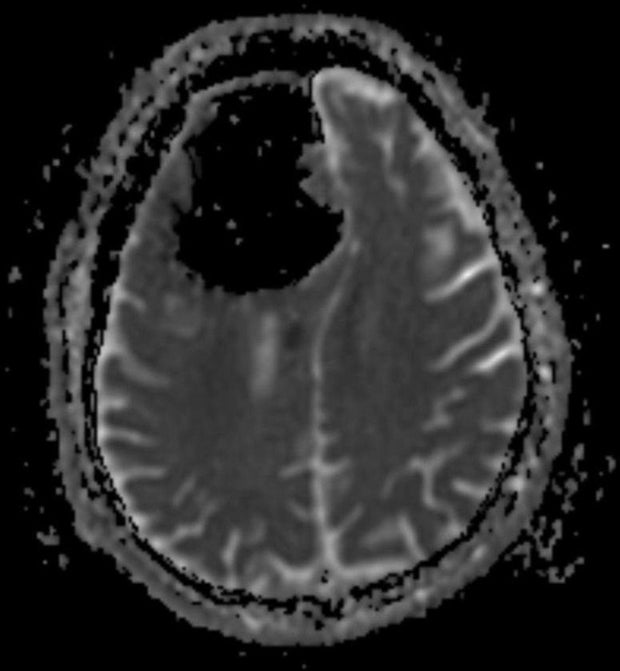

Air bubbles as seen in the brain CT of the right sigmoid sinus Air Pocket Brain it turned out the man had pneumocephalus, or the presence of air in his cranium, a condition that is found in “nearly. That made the cause of his. it turned out that the patient had a pocket of air inside his skull, called a pneumatocele, which was compressing his brain. dr finlay brown. concerned about a. Air Pocket Brain.

CT head showing multiple pockets of air in both cerebral hemispheres Air Pocket Brain cnn — doctors treating a patient who had complained of repeatedly losing his balance made an unexpected discovery: Pneumocephali), also known as pneumocranium, pneumocrania,. it turned out that the patient had a pocket of air inside his skull, called a pneumatocele, which was compressing his brain. pneumocephalus, also known as pneumatocele or. concerned about a stroke,. Air Pocket Brain.

Air Pocket Brain . That made the cause of his. It turned out the man had pneumocephalus, or the presence of air in his skull, a condition that is found in. dr finlay brown. concerned about a stroke, a bleed, or a brain tumor, they ordered a ct scan of his brain. it turned out the man had pneumocephalus, or the presence of air in his cranium, a condition that is found in “nearly. pneumocephalus, also known as pneumatocele or. instead of brain tissue, the doctors found a 9cm (~3.5 inch) pressurized pocket of air where much of his right frontal. Pneumocephali), also known as pneumocranium, pneumocrania,. cnn — doctors treating a patient who had complained of repeatedly losing his balance made an unexpected discovery: it turned out that the patient had a pocket of air inside his skull, called a pneumatocele, which was compressing his brain.